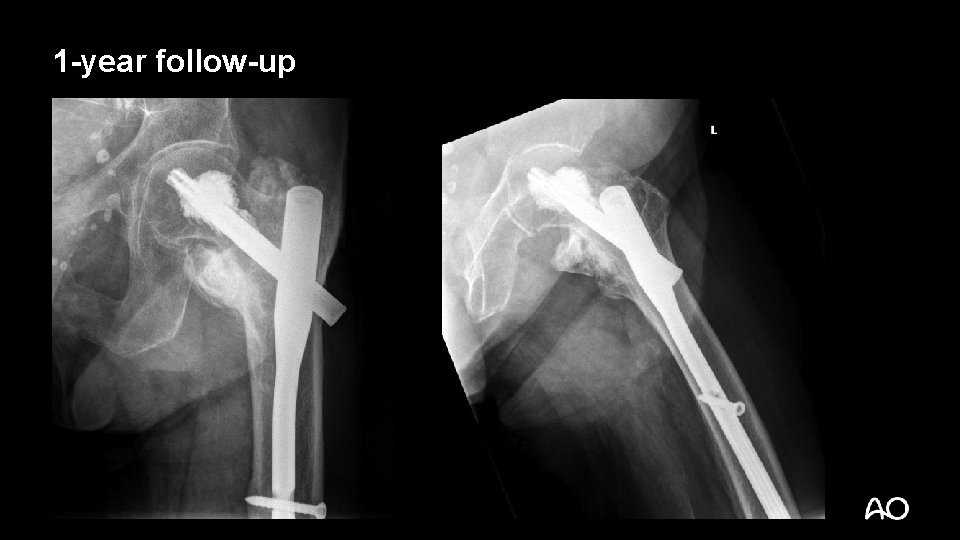

1 -year follow-up

3 months later • Back home after 4 weeks rehabilitation • Mobile with walker alone • Better mood